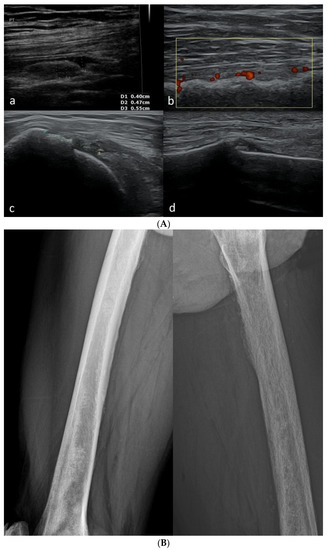

3.2.5. Osteochondroma

3.2.6. Exudates and Inflammations Affecting Joints